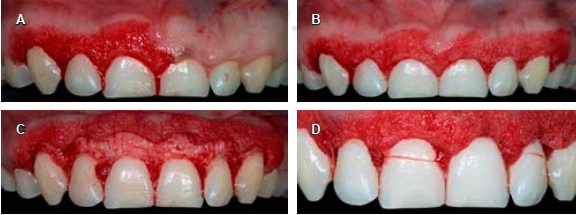

A continuación, con una sonda periodontal se marcó con puntos sangrantes la encía en la zona vestibular (según los datos obtenidos de la CBCT) de todos los dientes a tratar, en seguida se realizó una gingivectomía con una incisión a bisel interno con una hoja de bisturí No. 15c siguiendo el festoneo natural de la encía, y una incisión intracrevicular e incisión interdental; después se realizó una gingivoplastia a bisel interno con bisturí de Kirkland para disminuir el grosor de la encía insertada queratinizada y favorecer la posición de encía marginal con respecto a los cuellos de los dientes (Figura 4A y B). Se elevó un colgajo de espesor total (Figura 4C), se tomaron las medidas de la corona anatómica y se procedió a medir de la distancia de la cresta ósea a la UCE, corona clínica real, corona anatómica con la sonda periodontal (para así poder comparar los resultados obtenidos con CBCT). Por último, el colgajo se reposicionó y suturó con una técnica de sutura suspensoria, con hilo de sutura de ácido poliglicólico (VICRYL) de 4-0 (Figura 4D).

Figura 7 A) Medición de la cresta ósea a la unión cemento-esmalte con una sonda periodontal. B) Ostectomía realizada y medida con una sonda periodontal. C) Vista transversal en cone-beam computed tomography de pieza 2.1 con la distancia (0.83 mm) de la unión cemento-esmalte a cresta ósea.